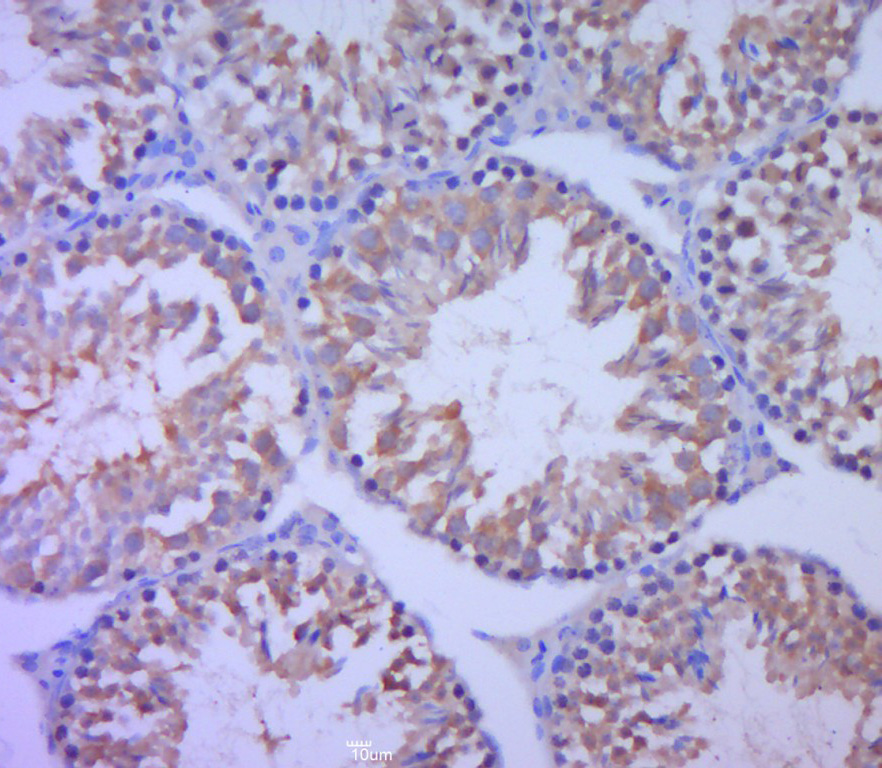

Paraformaldehyde-fixed, paraffin embedded (mouse testis tissue); Antigen retrieval by boiling in sodium citrate buffer (pH6.0) for 15min; Block endogenous peroxidase by 3% hydrogen peroxide for 20 minutes; Blocking buffer (normal goat serum) at 37°C for 30min; Antibody incubation with (cIAP1) Polyclonal Antibody, Unconjugated (bs-4262R) at 1:400 overnight at 4°C, followed by a conjugated secondary (sp-0023) for 20 minutes and DAB staining.